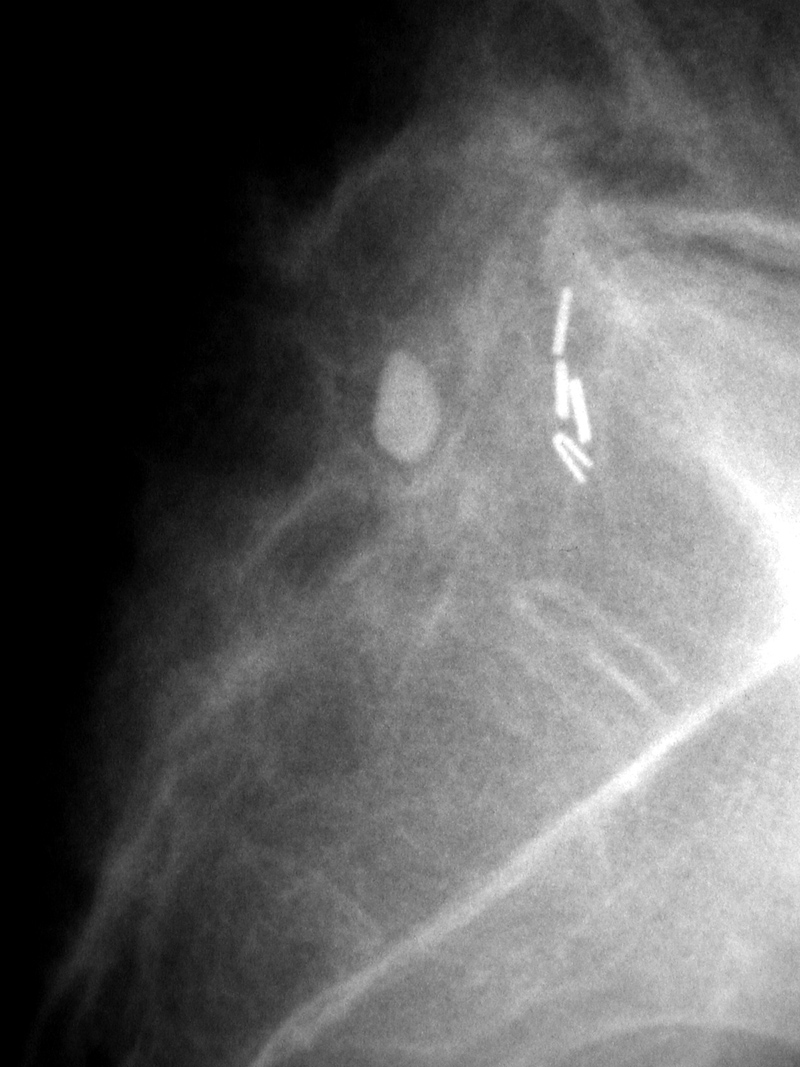

Intrathecal drug delivery catheter (arrow) |

The catheter is in the lower thoracic subarachnoid space. It exits into an anterior abdominal delivery pump. From Hunter, 2004 |